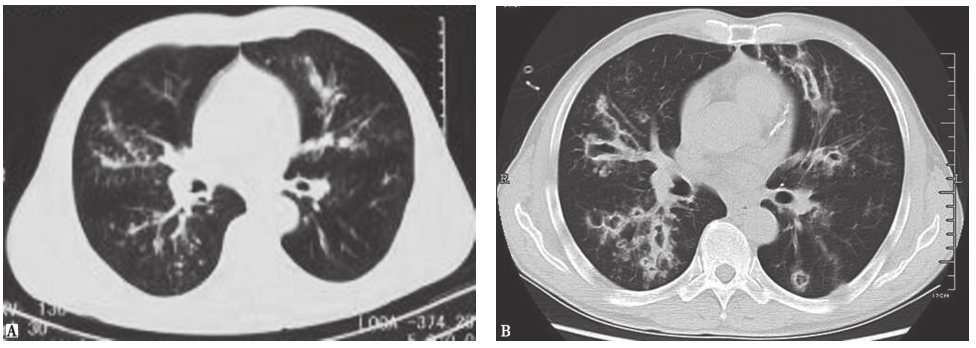

图2侵袭性肺曲霉菌病胸部CT表现

男患者性,53岁,发热、咯血1周,伴呼吸困难,诊断为侵袭性肺曲霉菌病。胸部CT初期表现为沿支气管分布的粟粒样结节(A);1周后表现为多发沿支气管分布的空洞,有中心性支气管扩张(B)

图3血源性金黄色葡萄球菌肺炎胸部CT表现

胸部CT可见双肺多发结节空洞性改变,部分空洞伴液平,病灶周围可见渗出表现